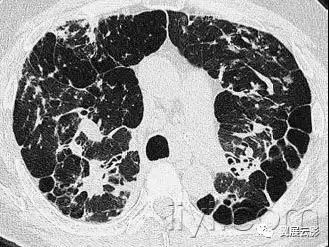

十八、小叶中心性:

解剖:小叶中心性用于描述次级肺小叶的支气管血管束中心区域。病理学上也用这一术语描述终末小支气管远端,位于呼吸性细支气管和肺泡管中心的病变。

CT:正常次级肺小叶中心的点状或者线状的密度增高影,胸膜下25px范围内最明显,代表小叶内的动脉,直径约1mm。

小叶中心性异常包括(1)结节(2)树芽征,提示小气道病变(3)由于临近间质的增厚或者浸润导致小叶中心结果更加清晰(4)小叶中心性肺气肿导致的异常低密度。

附图为小叶中心性肺气肿